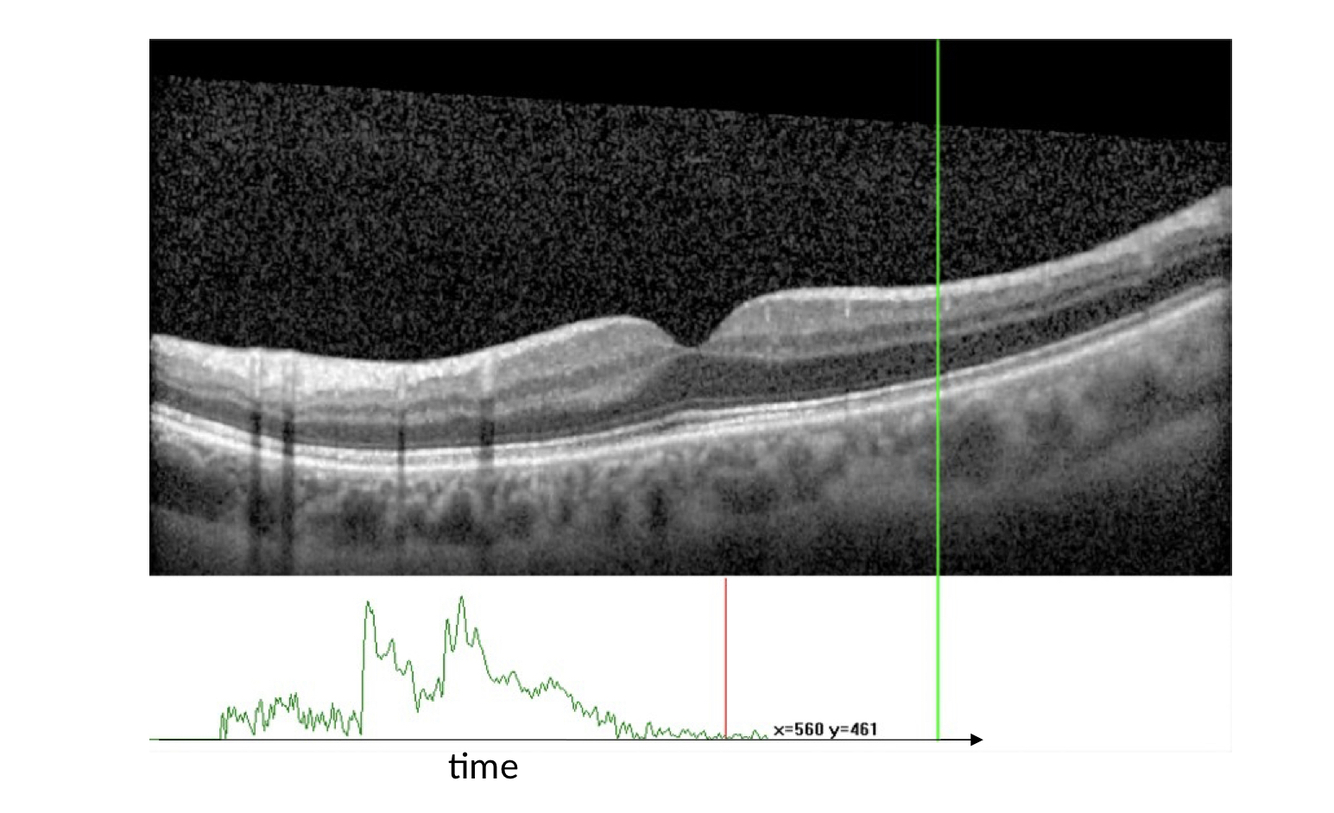

This is a nice way of what an OCT shows, just for your information

What does the green line show?

A

An A scan